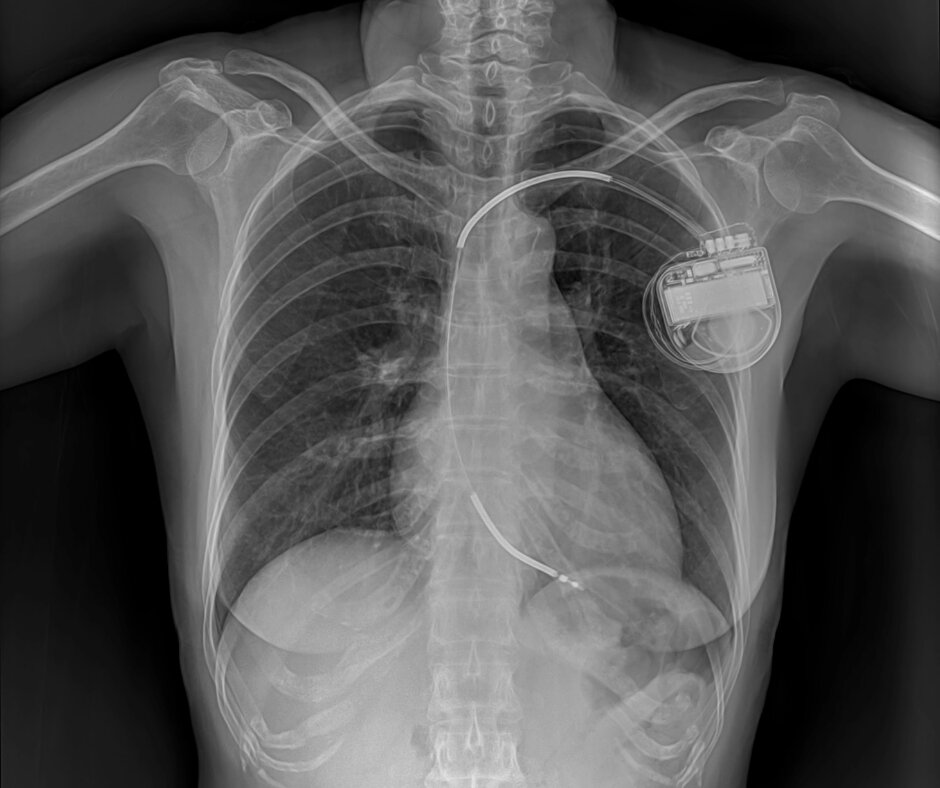

Pacemaker | Dr.Ishwar Zanwar

A pacemaker is a small device that is surgically implanted under the skin of the chest. It's designed to help regulate the heartbeat for people who...

Pacemaker implantation

Pacemaker implantation is a surgical procedure where a small electrical device called a pacemaker is implanted in your chest. The pacemaker sends regular electrical pulses that help keep your heart beating regularly.